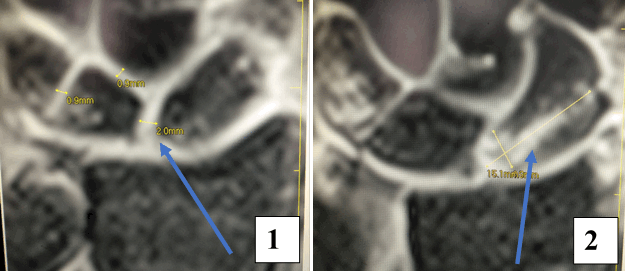

Результат МРТ правого лучезапястного сустава (рис. 2), подтвердил клиническое предположение о повреждении ладьевидно-полулунной связки, который заключался в нарушении целостности структуры связки. Также были выявлены признаки асептического некроза ладьевидной кости в стадии отека костной ткани.

Рис. 2. МРТ-исследование правого лучезапястного сустава. Получены протон взвешенные изображения с подавлением сигнала от жировой ткани (PD FAT SAT) в аксиальной, сагиттальной и фронтальной плоскостях, Т1 взвешенные изображения во фронтальной плоскости. На полученных сканах определяется: 1 – увеличение ладьевидно-полулунного сустава вдвое по сравнению с соседними; 2 – вдоль оси ладьевидной кости отмечается скопление жидкости, что можно расценить, как продольный перелом ладьевидной кости, либо отек костной ткани